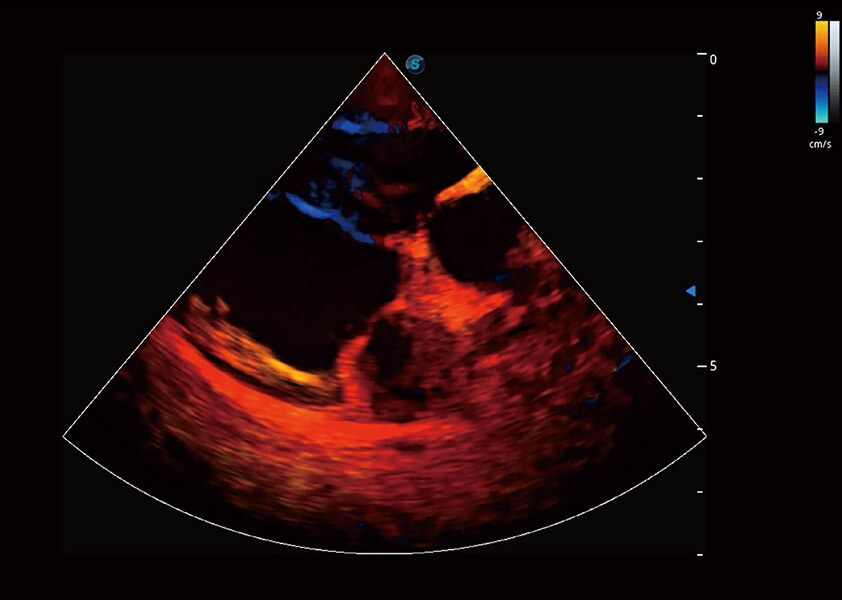

ProPet 60 作為一款高端臺(tái)式動(dòng)物超聲設(shè)備,為動(dòng)物醫(yī)生的日常診斷提供了一系列貼合動(dòng)物臨床需求、解決臨床實(shí)際問題的高級(jí)成像功能。憑借全系列高清探頭,滿足醫(yī)生對(duì)腹部、心臟、生殖、淺表、肌骨等成像的所有需求,切實(shí)幫助您提升檢查效率,提高診斷信心。